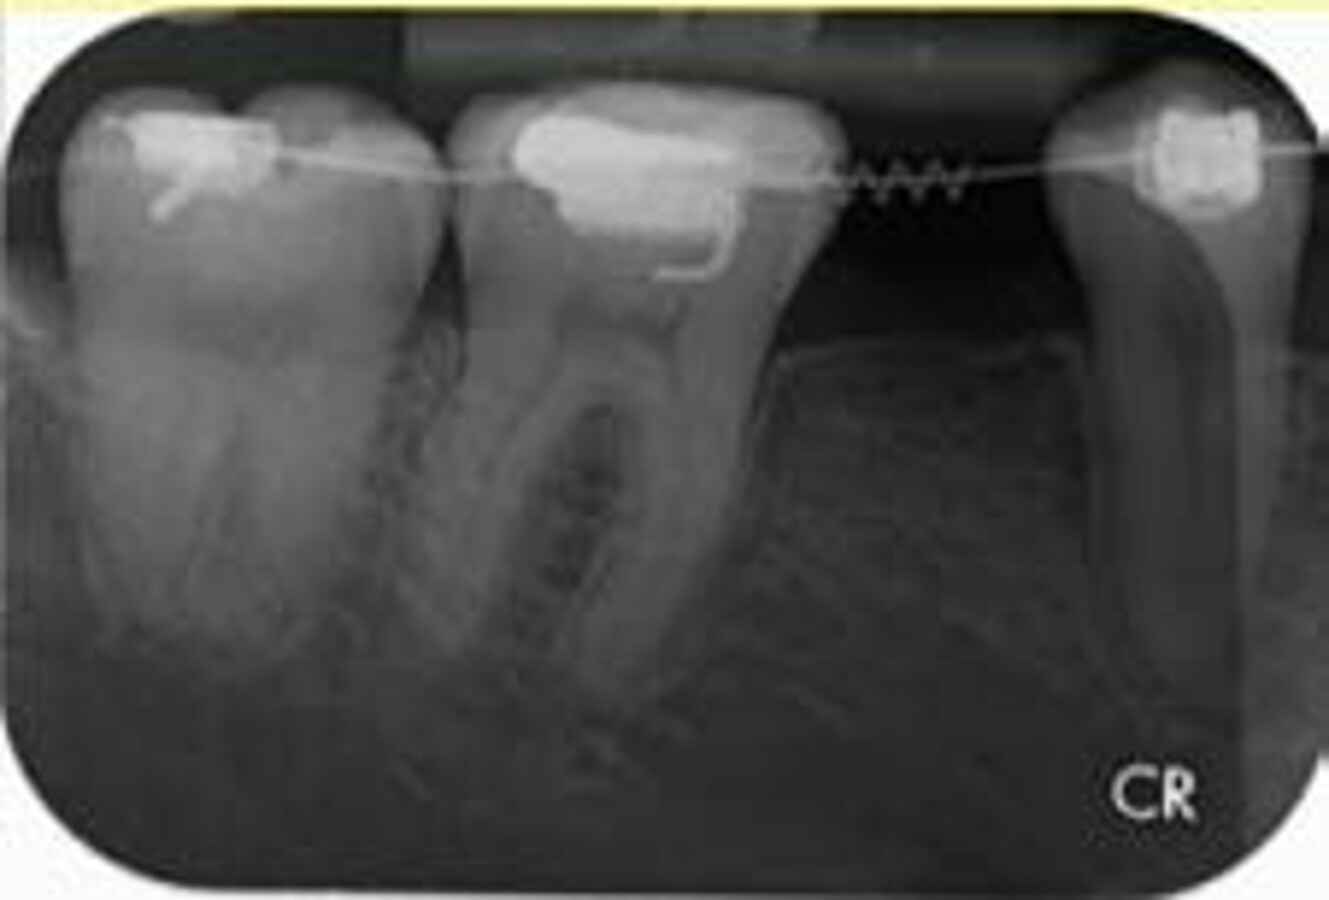

Fig. 3: Pre-operative IOPA of edentulous site 35